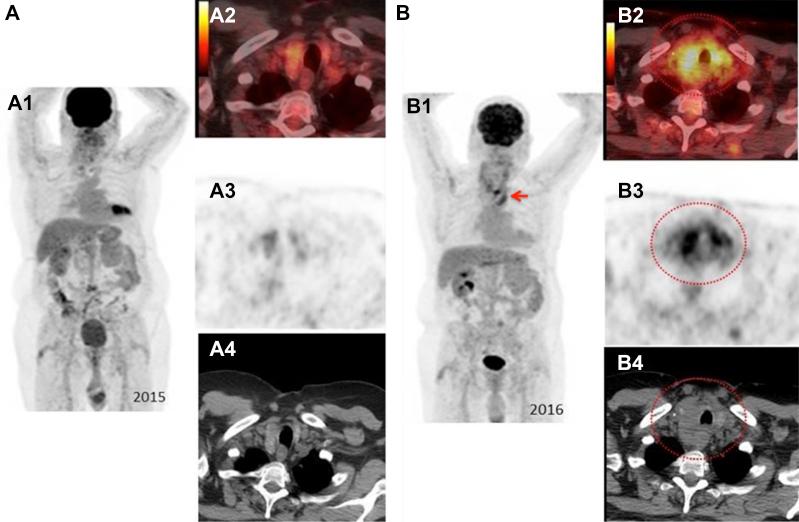

Diffuse thyroid metastases and bilateral internal jugular vein tumor thrombus from renal cell cancer.

Renal cell cancer rarely metastasizes to the thyroid gland, and it has been reported to present as a solitary mass. We present a case of diffuse thyroid cancer metastases from renal cell cancer. Bilateral internal jugular vein tumor thrombi were also present. To the best of our knowledge, this is the first description of diffuse thyroid metastases from renal cell cancer in the English literature. Renal cell cancer metastases should be considered in the differential of thyroid imaging abnormalities arising in the setting of known renal cell carcinoma, particularly late in the course of disease. This is frequently associated with internal jugular vein thrombi, which should be evaluated with an abnormal thyroid. Thyroglobulin levels are usually normal in such patients.